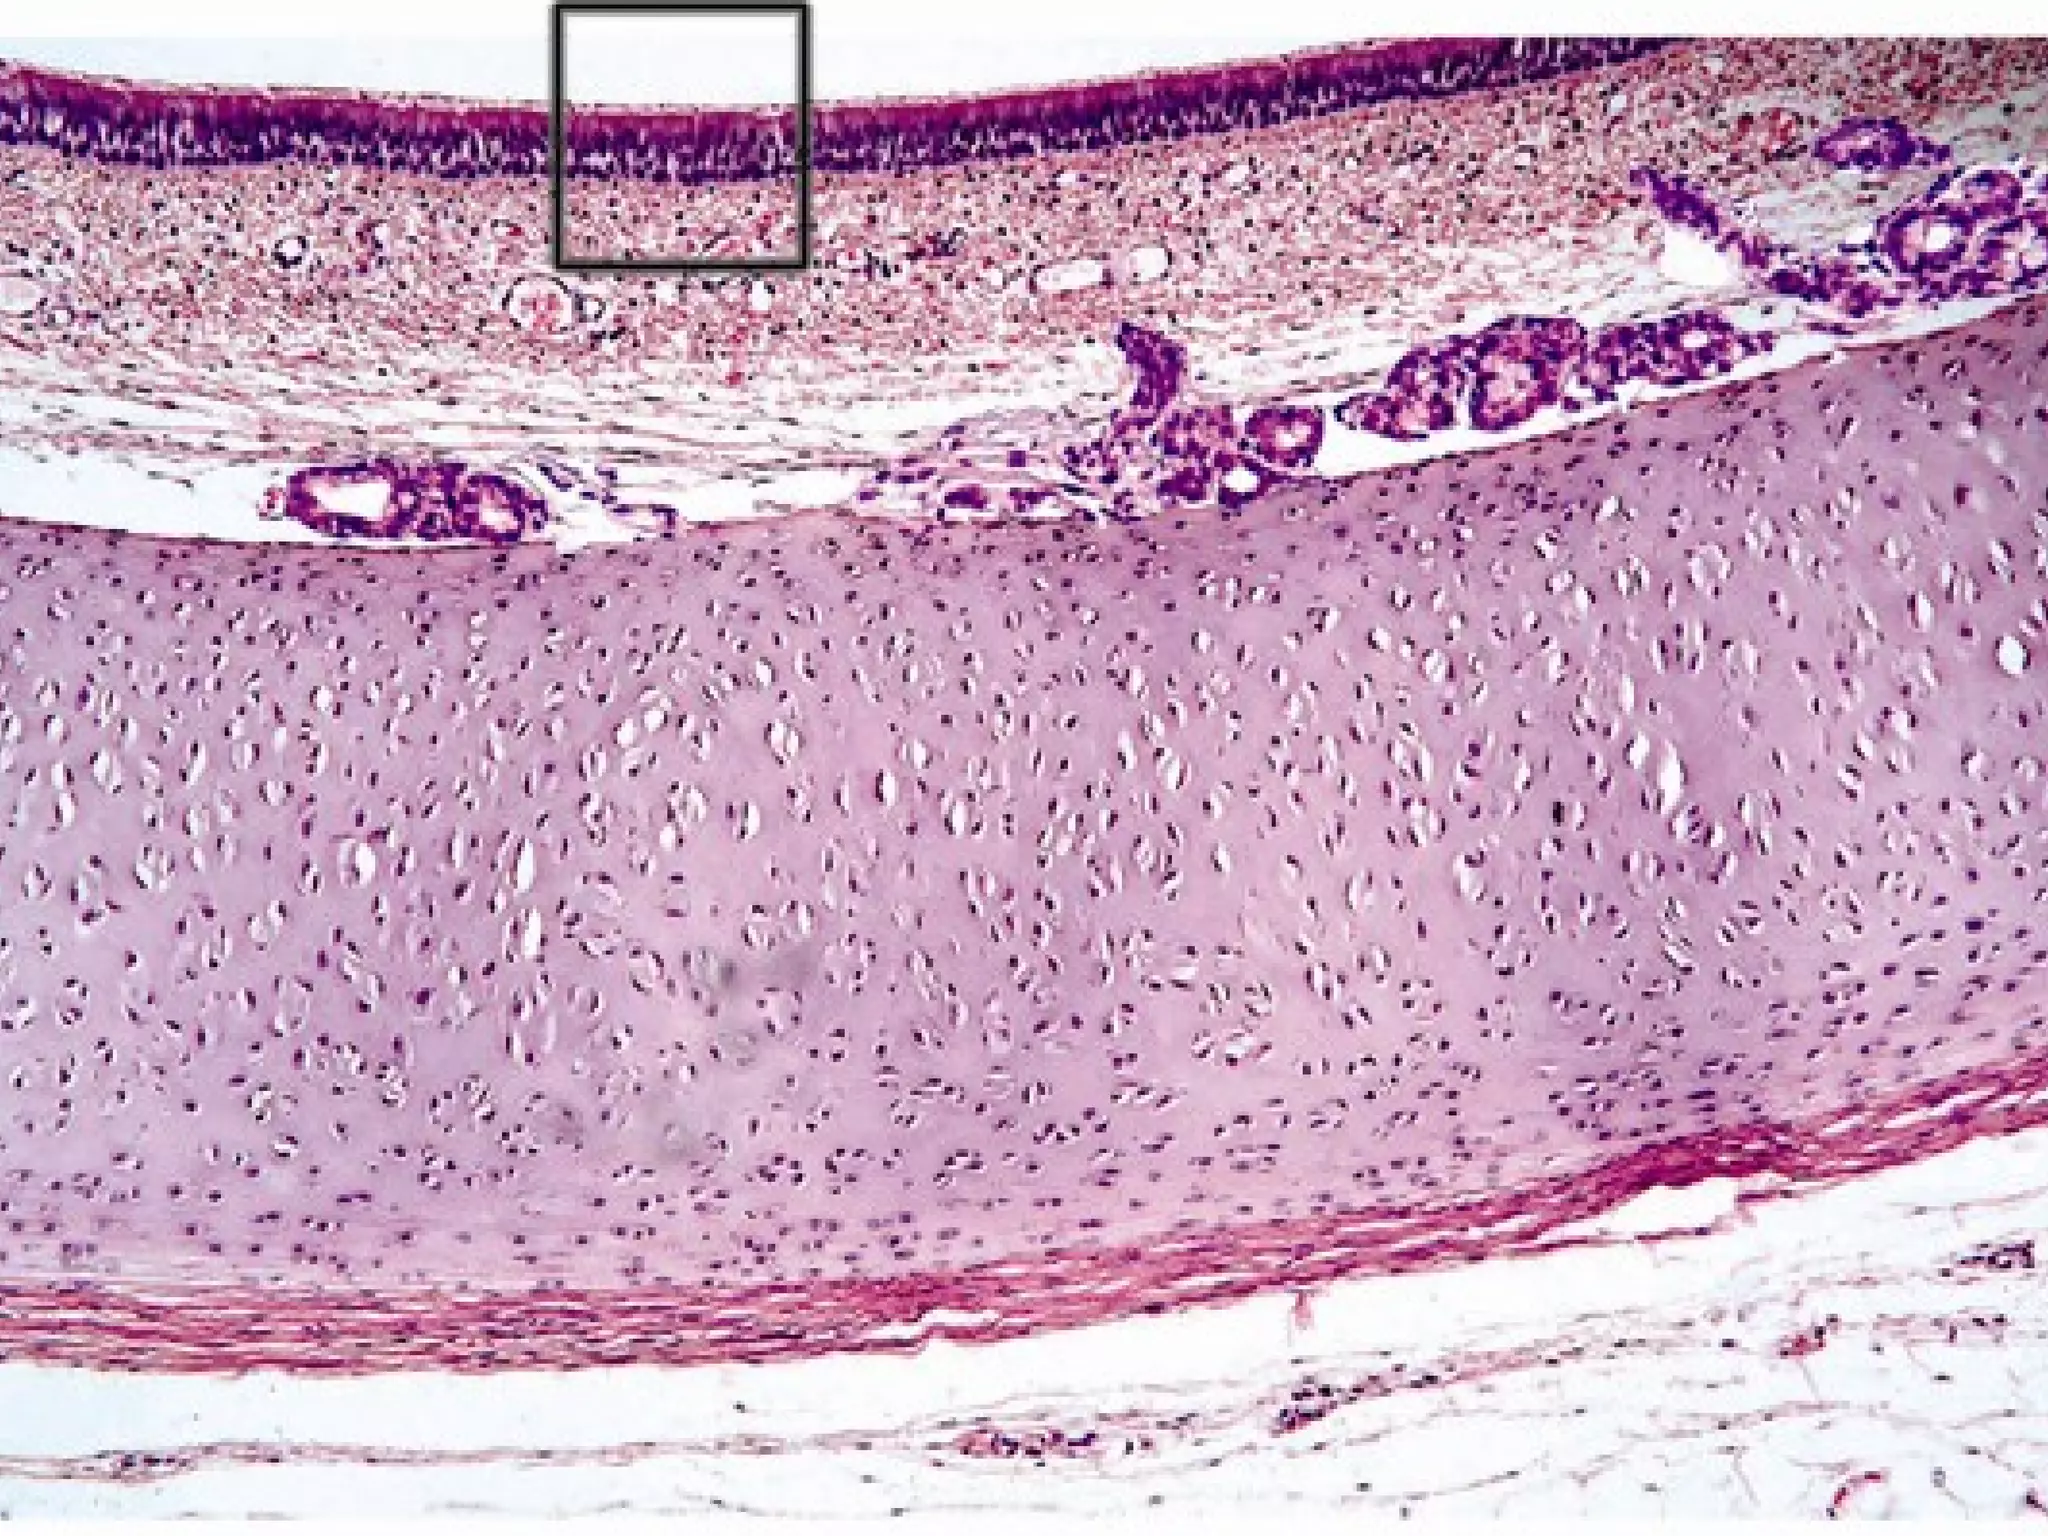

This document outlines several human body systems including the vascular, lymphatic, respiratory, digestive, and endocrine systems. It describes the trachea and lungs in the respiratory system, the oral cavity and digestive glands in the digestive system, and mentions the parotid, pancreas, and classic hepatic lobule in relation to the digestive system and endocrine glands.